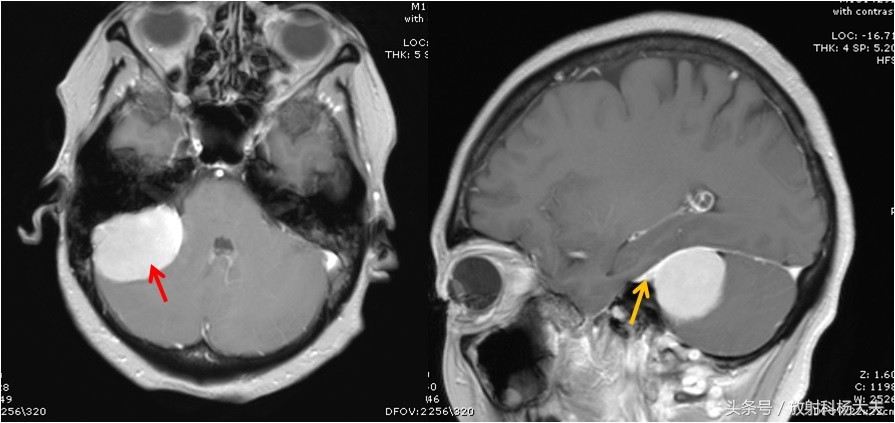

左图为轴位图像,显示强化的脑膜瘤。右图为矢状位,黄箭所示为脑膜尾征。

但有一点请大家注意,这个征象一定要考增强扫描才能看到,如下图,为本例的平扫图像,是无法准确观察脑膜尾征的。